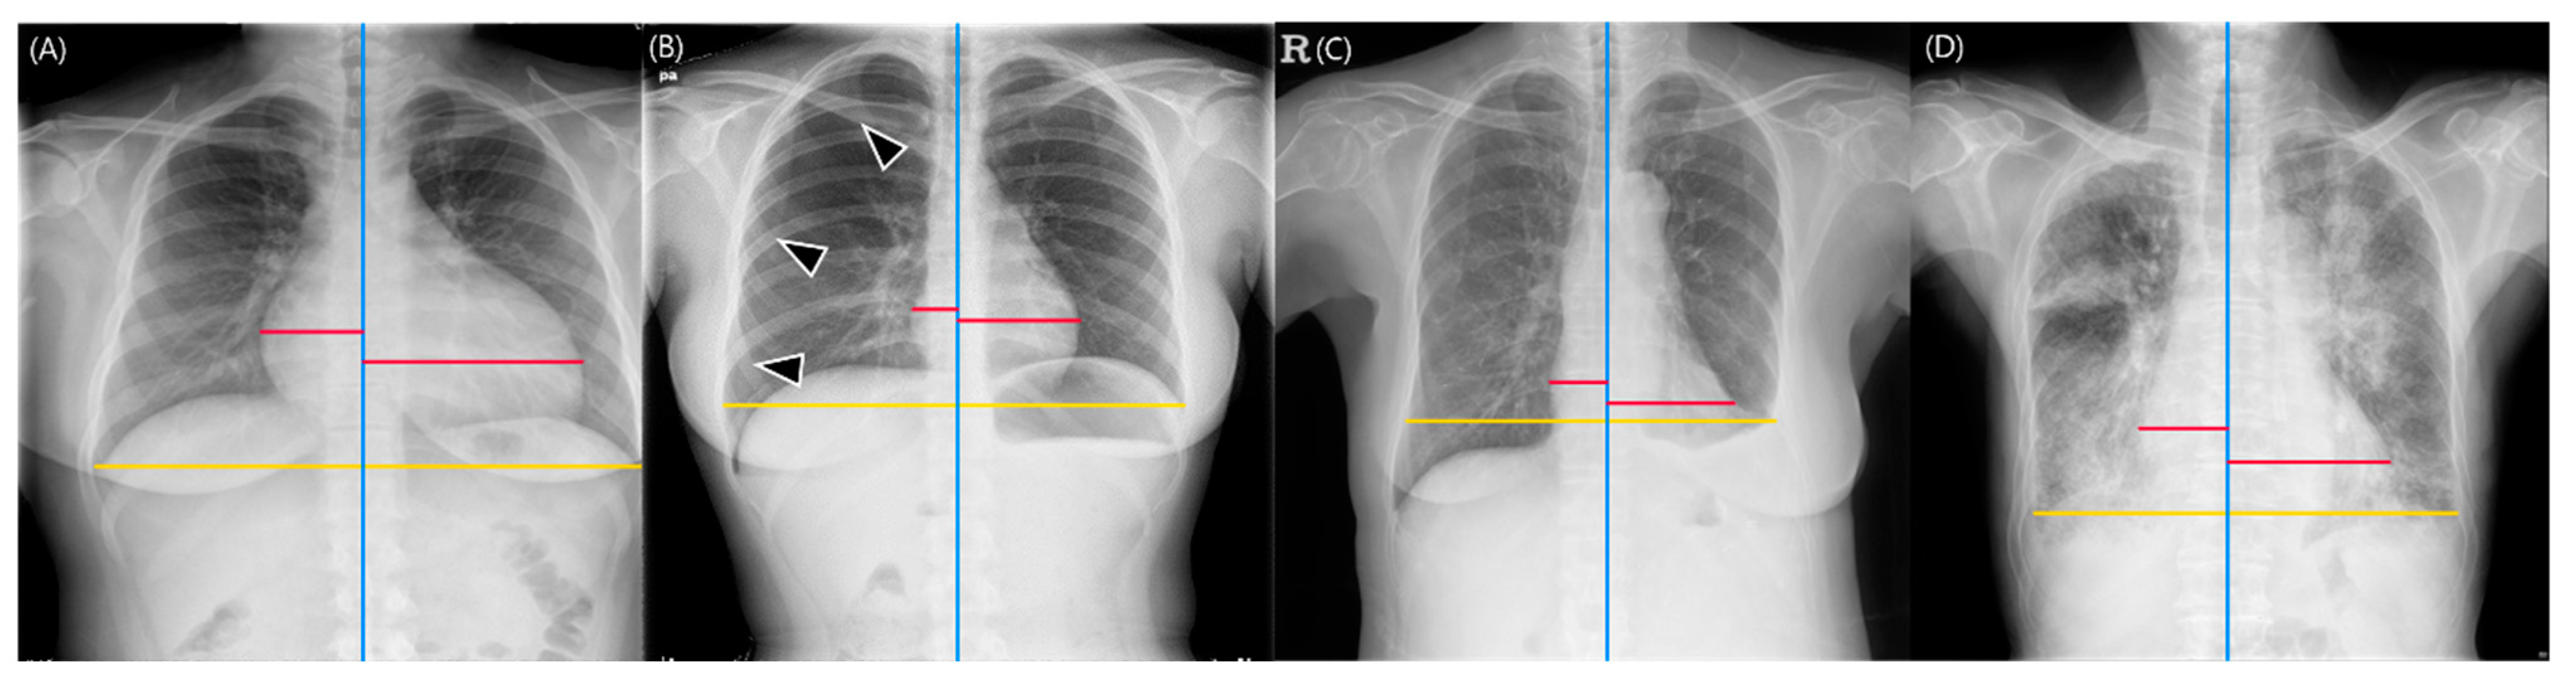

2.2. Study Sample